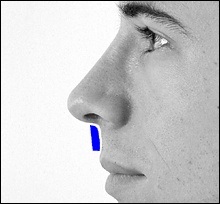

Része a gerinc, amelyeket el kell távolítani jelzi a kék vonalon. Removal végezzük vésővel.

A fotó távoli nazális gerinc. On line távolság centiméterben, és a fekete nyíl képviseli a távolság egy inch.

A jobb felső sarokban a kép jól látható acanthion (sárga színnel jelöltek). Az alsó képen az azonos, de a távoli nazális gerinc.

A hossza a kék nyíl egyenlő egy hüvelyk.